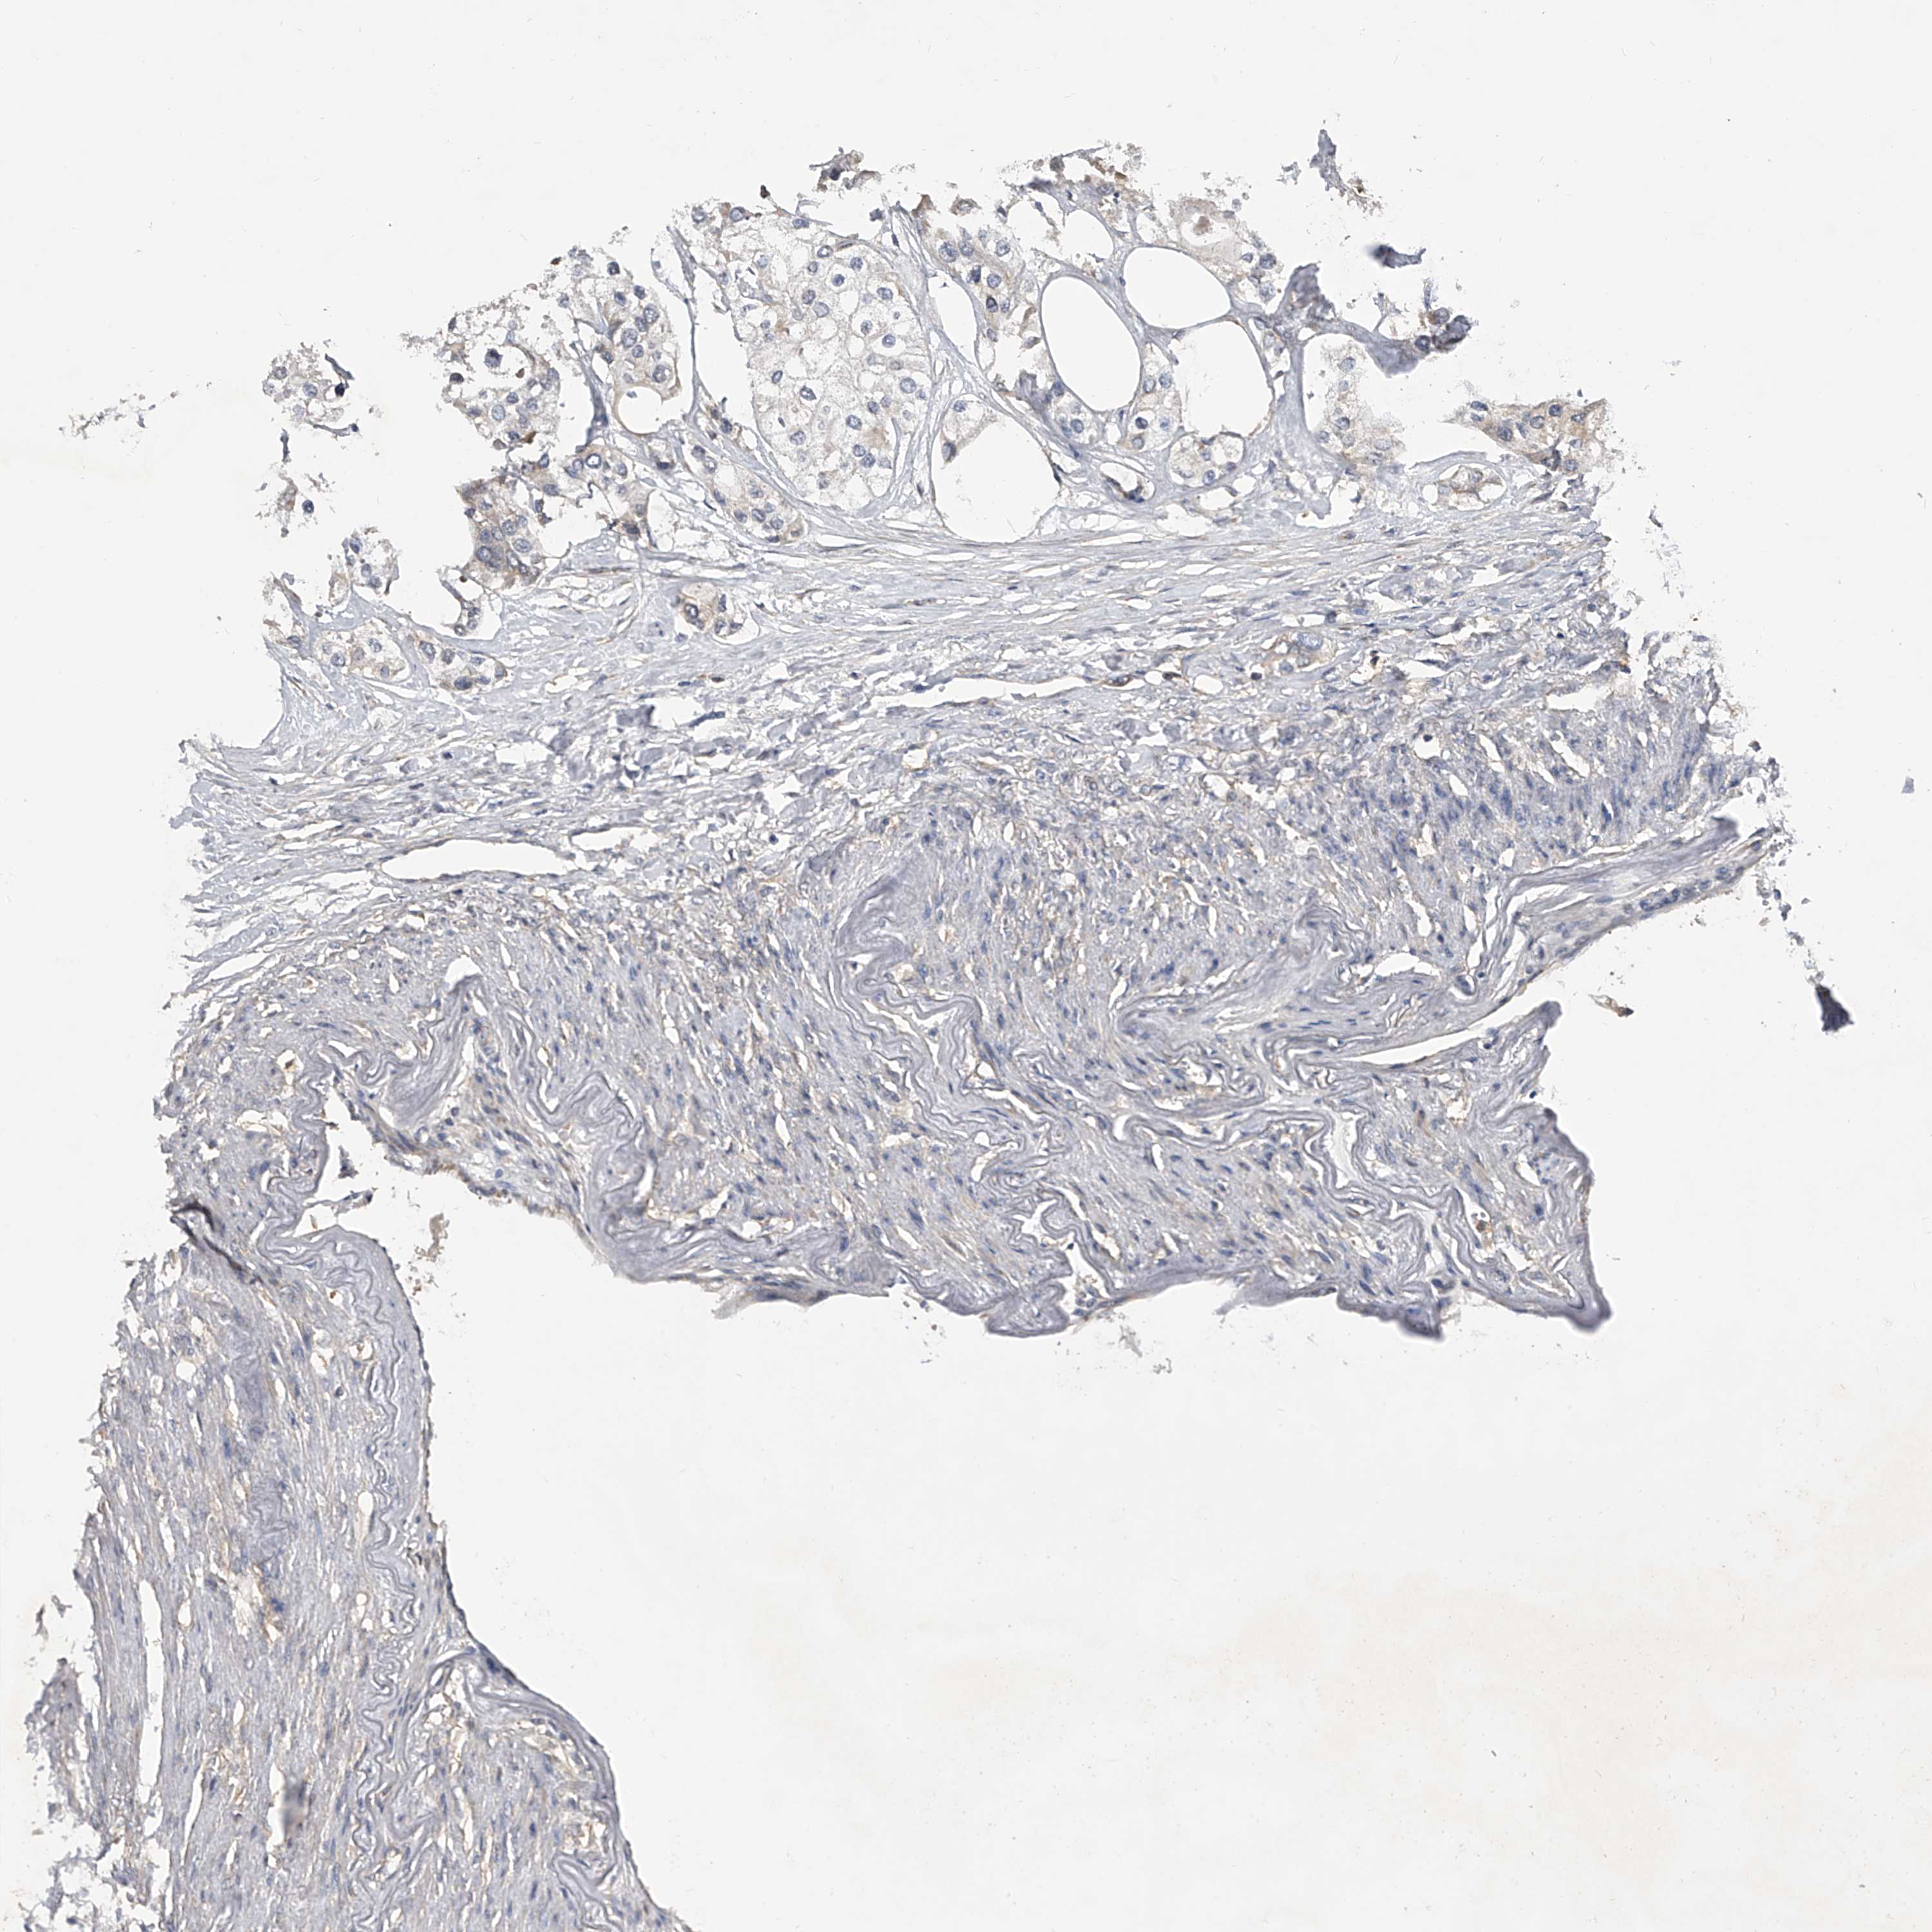

UROTHELIAL CANCER - Protein expressioni

A mouse-over function shows sample information and annotation data. Click on an image to view it in a full screen mode. Samples can be filtered based on level of antibody staining by selecting one or several of the following categories: high, medium, low and not detected. The assay and annotation is described here.

Note that samples used for immunohistochemistry by the Human Protein Atlas do not correspond to samples in the TCGA dataset.

Antibody stainingi

Antibody staining in the annotated cell types in the current human tissue is reported as not detected, low, medium, or high, based on conventional immunohistochemistry profiling in selected tissues. This score is based on the combination of the staining intensity and fraction of stained cells.

Each image is clickable and will lead to virtual microscopy that enables deeper exploration of all samples and also displays staining intensity scores, fraction scores and subcellular localization as well as patient and tissue information for each sample.

Antibody HPA029412

Antibody CAB034366

Staining

High

Medium

Low

Not detected

Intensity

Strong

Moderate

Weak

Negative

Quantity

>75%

75%-25%

<25%

None

Location

Nuclear

Cytoplasmic/membranous

Cytoplasmic/membranous,nuclear

Urothelial carcinoma, Low grade

Urothelial carcinoma, High grade